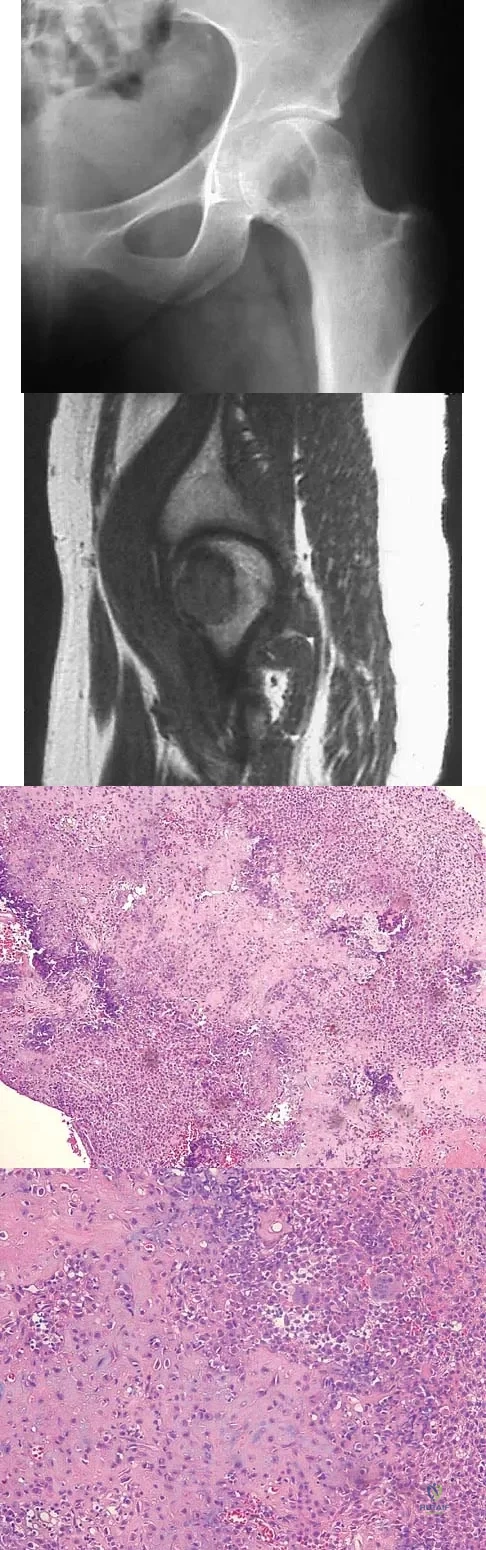

A 13-year-old girl has had right groin pain for the past 3 weeks. She denies any history of trauma. Examination of the hip reveals no palpable soft-tissue mass or lymphadenopathy, and there is full range of motion. A plain radiograph and MRI scan are shown in Figures 15a and 15b. Biopsy specimens are shown in Figures 15c and 15d. What is the most likely diagnosis?

Explanation